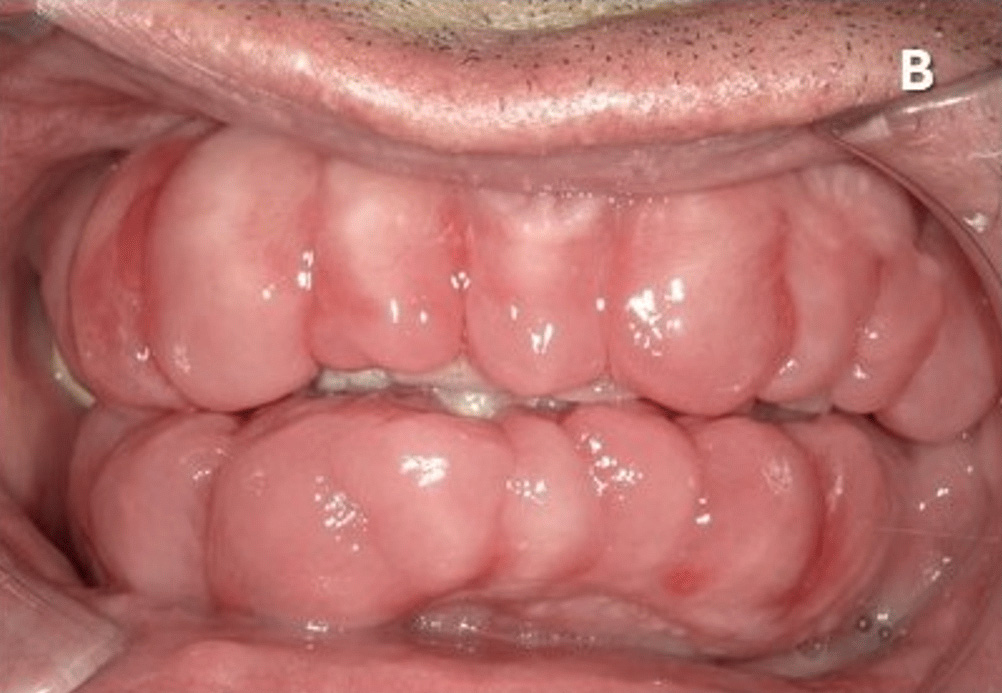

覚醒剤を乱用した61歳の男性の歯茎を撮影した画像。

5年間の覚醒剤使用とホームレス生活により口腔衛生不良があり、歯肉の肥大、疼痛、出血による咀嚼困難で病院へ。